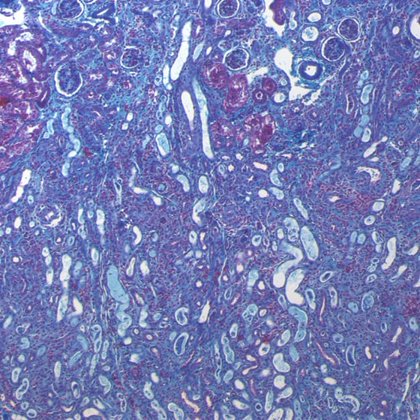

A new monoclonal antibody #drug developed by scientists in the Yale Department of Immunobiology reverses the #scarring caused by #fibrotic diseases like #scleroderma. Their findings could be applied to future, lifesaving therapies:

A Yale-led team developed a therapeutic antibody for the treatment of fibrosis and identified another promising target for future therapies.